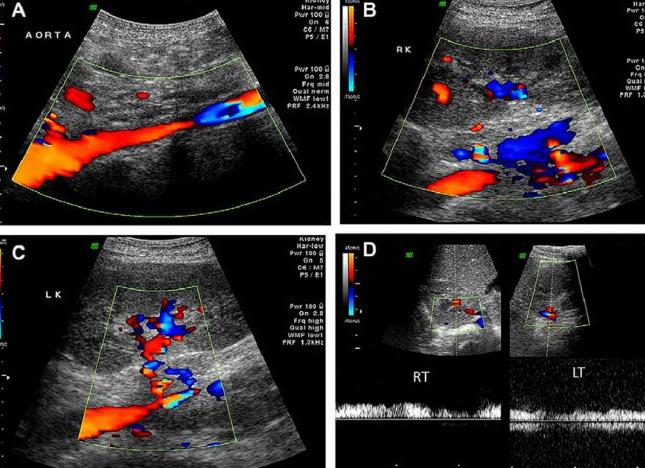

Что такое ЦДК

Цветовое допплеровское картирование (ЦДК) – это один из подвидов УЗИ, основанного на эффекте Допплера. Оно также «работает» с оценкой кровотока в сосудах.

В основе данного исследования – совмещение обычного черно-белого УЗИ и допплеровской оценки кровотока.

В режиме ЦДК врач видит на мониторе черно-белое изображение, в определенной (исследуемой) части которого отображаются в цвете данные скорости движения структур.

Так, оттенки красного цвета будут кодировать скорость течения крови, направленного к датчику (чем светлее, тем меньше скорость), оттенки голубого цвета – скорость кровотока, направленного от датчика. Рядом выводится шкала, на которой обозначено, какой именно скорости соответствует тот или иной оттенок. То есть, синим цветом обозначены не вены, а красным – не артерии.

Цветовое допплеровское картирование визуализирует и анализирует:

• степень утолщения сосудистой стенки

• пристеночные тромбы или атеросклеротические бляшки (может их отличить)

• патологическую извитость сосуда

• аневризму сосуда.

Цветовое допплеровское картирование

ЦДК или так называемый «цветовой допплер» показывает движение крови в визуально понятном виде. На экране во время проведения ЦДК разнонаправленные потоки изображены разными цветами — красным и синим. Причем их оттенки зависят о того, как быстро «бежит» кровь. ЦДК используют не только для исследования кровотока в сосудах, но и в эхокардиографии. Метод ЦДК в сочетании с дуплексной допплерометрией обозначают как триплексное сканирование.

Цветовое допплеровское картирование – это ультразвуковой метод визуализации тока крови. Он основан на определении скорости кровотока, кодировании данных о скорости с применением разных цветов. Полученная картина скорости кровотока накладывается на монохромное двухмерное изображение сосудов исследуемой зоны.

Определение скорости кровотока и состояния сосудов

Исследование потоков крови проводится в средних и крупных сосудах, реже – в мелких. Красным цветом кодируется поток, направленный в сторону датчика ЦДК, синим цветом кодируется обратный поток. Темные оттенки этих цветов проявляются в зонах с низкими скоростями, светлые – с высокими. Исследование с применением цветового допплеровского картирования позволяет определить не только скорость кровотока в сосудах, но и состояние сосудов, их сокращаемость, выявить патологии.